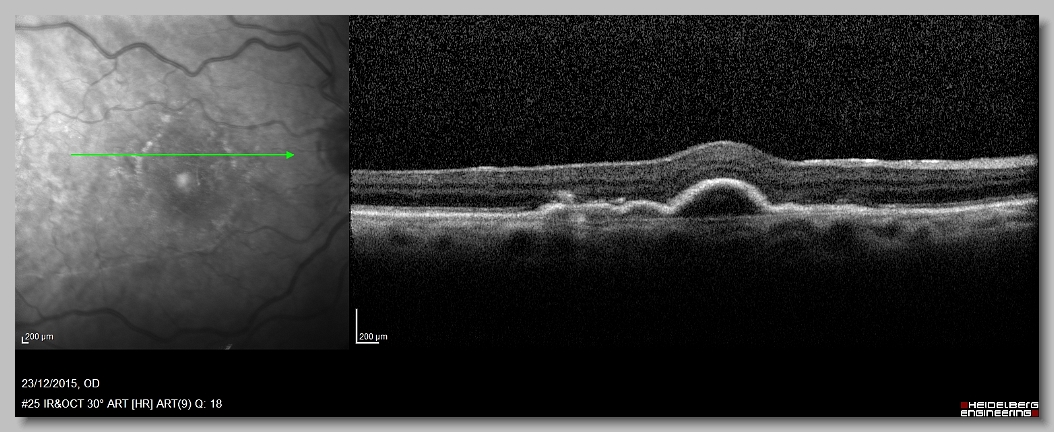

OCT 23-12-2015